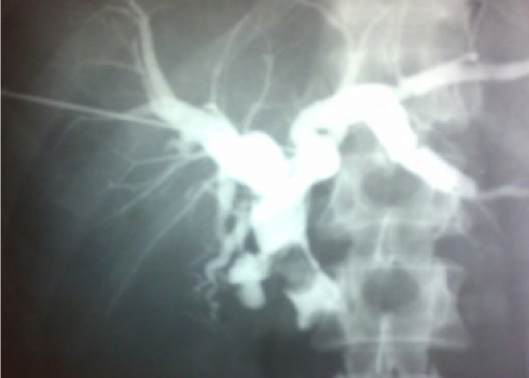

b) Magnetic resonance imaging (MRI): magnetic resonant cholangiopancreatography (MRCP) is non-invasive tool to assess the biliary system. MRI can assess for any lesion causing biliary obstruction such as pancreatic tumor or cholangiocarcinoma.

MRCP showing stone in the common bile duct and in the gallbladder

MRCP study - stone in GB z

Double duct sign and stricture at the lower end of CBD strongly suggest carcinoma of pancreas

-

Note: Double duct sign Z shows that CBD and PD are both dilated

The width of a normal pancreatic duct is 3â4 mm Z